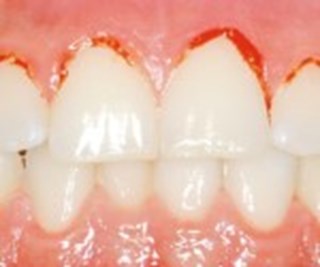

Ett inflammerat tandkött kan se helt friskt ut.

Petar man på ett inflammerat tandkött så blöder det.

Inflammerat tandkött

En inflammation i tandköttet kan vara början till parodontit. Och det är placket som bildas i munnen som är orsaken till tandköttsinflammation (gingivit). Inflammation utan parodontit är enkel att behandla. Med förbättrad munhygien läker det oftast ut på en eller ett par veckor. Dock kan inflammationen komma tillbaka snabbt om munhygienen försämras. Noggrann rengöring med tandborste, tandtråd eller liknande är det enklaste knepet för att undvika inflammerat tandkött.